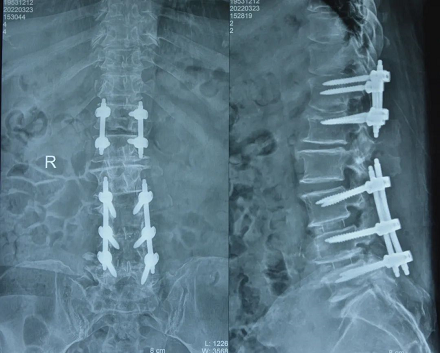

经详细查体、反复会诊,及充分的术前准备,脊柱外科韦向荣主任带领的脊柱外科团队为姜阿姨实施了“后路切开全椎板减压植骨融合椎弓根钉棒内固定术”。严重的胸椎疾病,要比颈、腰椎手术难度更大、风险更高。骨科医生之间流传着一句话“宁割十个脖子,不割一个胸椎”,意思是说相比颈椎手术,胸椎手术由于操作空间狭小,稍有不慎损伤到椎管内的脊髓及周围血管就会造成严重后果。而姜阿姨属于高位胸椎管狭窄(胸椎T12、腰L1节段),手术难度更高,对医生技术要求更是不言而喻。

患者术后影像

经过5个小时的手术,手术顺利完成。当从麻醉状态苏醒来时,姜阿姨的第一反应是自己的双腿没瘫,而且明显比术前轻松了。“原本我还挺担心自己会再也站不起来了,没想到这么快就可以下床站立、活动!早知道我前几年就该过来看了!”患者和家属非常高兴,对手术效果表示十分满意。